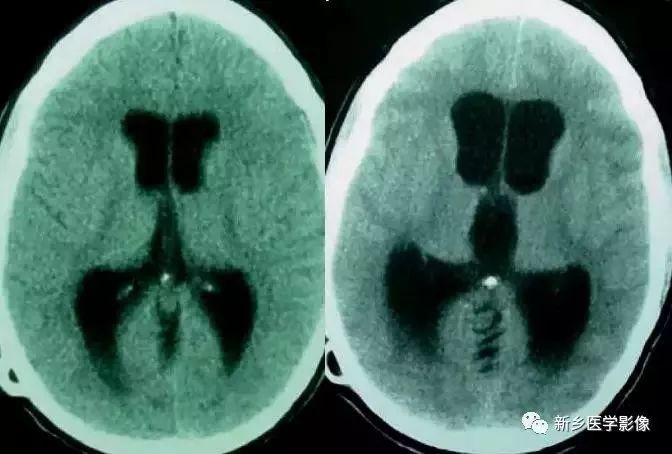

前脑无裂畸形(holoprosencephaly):

是指一系列位于中线程度不同的畸形,累及大脑、面部、脑于和小脑。前脑未能够分开,呈不全性或完全性,端脑和间脑无法区分。根据脑及面部畸形程度将其分为无叶型、半叶型和单叶型。

- 无叶型前脑无裂畸形:最严重,端脑半球间没有裂隙,呈马蹄形或新月形扩大的单脑室跨越中线,与背侧囊交通。丘脑互相融合,面部畸形可有两眼距离过近、独眼畸形等。往往死于胎儿或新生儿期。

- 半叶型前脑无裂畸形:在前脑可见部分裂隙, 形成不同发育程度的大脑纵裂及大脑镰。两侧大脑半球在前部未完全分开,但枕叶和 双侧侧脑室体部分离,丘脑分开不完全。三脑室和海马发育不全,胼胝体仅可见到压部,而其他部分缺如额叶和基底节前部分辨不清。临床表现有两眼距离过近、唇裂、腭裂等面部畸形,侧脑室呈单一性且明显扩大。

- 单叶型前脑无裂畸形:与正常发育脑仅有些很小的区别,如透明隔缺如或双侧额叶不完全分开。